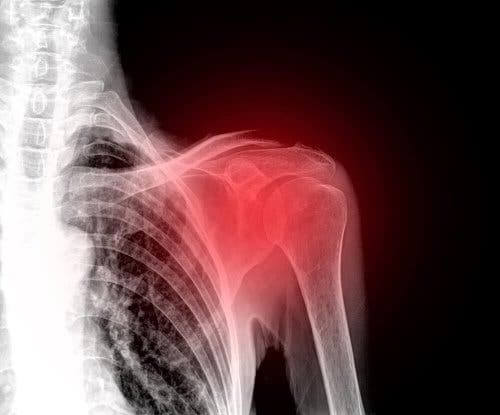

Rotator Cuff læsion: Det skal du vide

En rotator cuff læsion er en skade, der ofte rammer middelaldrende skuldre. Således er det i øjeblikket en af de førende årsager til skuldersmerter.

Desværre er skulderen en del af kroppen, der har tendens til atrofi, og dette fører ofte til ubehag. Faktisk er en skade på dette område virkelig deaktiverende og smertefuld. Derfor vil vi i denne artikel forklare alt, hvad du har brug for at vide om rotator cuff læsioner.